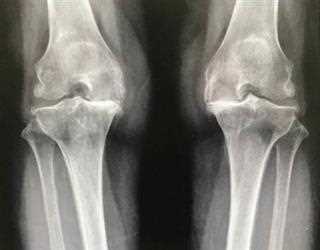

Osteoarthritis – Is it just a degenerative process?

By far Osteoarthritis, is the most common joint disorder worldwide. It is truly universal condition, affecting both sexes and all races. Evidences suggest that